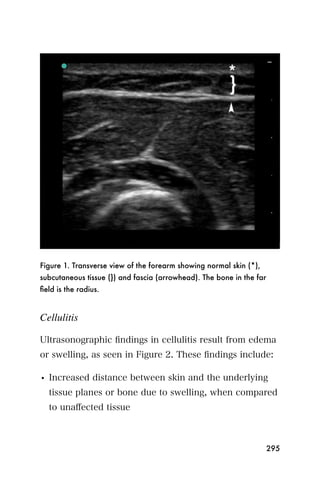

6. Rotate the probe 90 degrees until a transverse view of

the gallbladder is obtained. Fan through the

gallbladder to examine the entire organ. Gallstones

will appear hyperechoic with an anechoic or

hypoechoic shadows, as seen in Figure 14.